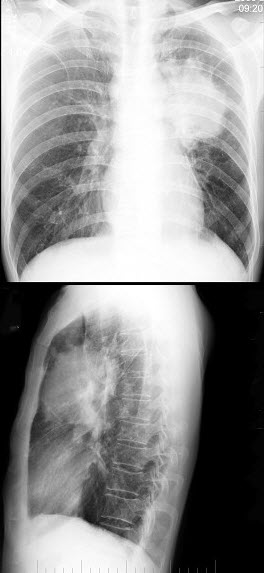

40、单项选择题

男,8岁,胸闷、气急1月余,查体见颈静脉显露,胸片如图,最可能的诊断是()

A.心包积液

B.心肌炎

C.淋巴瘤

D.房间隔缺损

E.肺静脉异位引流